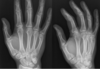

Perfectly

**Psoriatic arthropathy** Pencil in cup X-ray showing some of changes in seen in psoriatic arthropathy. Note that the DIPs are predominately affected, rather than the MCPs and PIPs as would be seen with rheumatoid. Extensive juxta-articular periostitis is seen in the DIPs but the changes have not yet progressed to the classic 'pencil-in-cup' changes that are often seen.